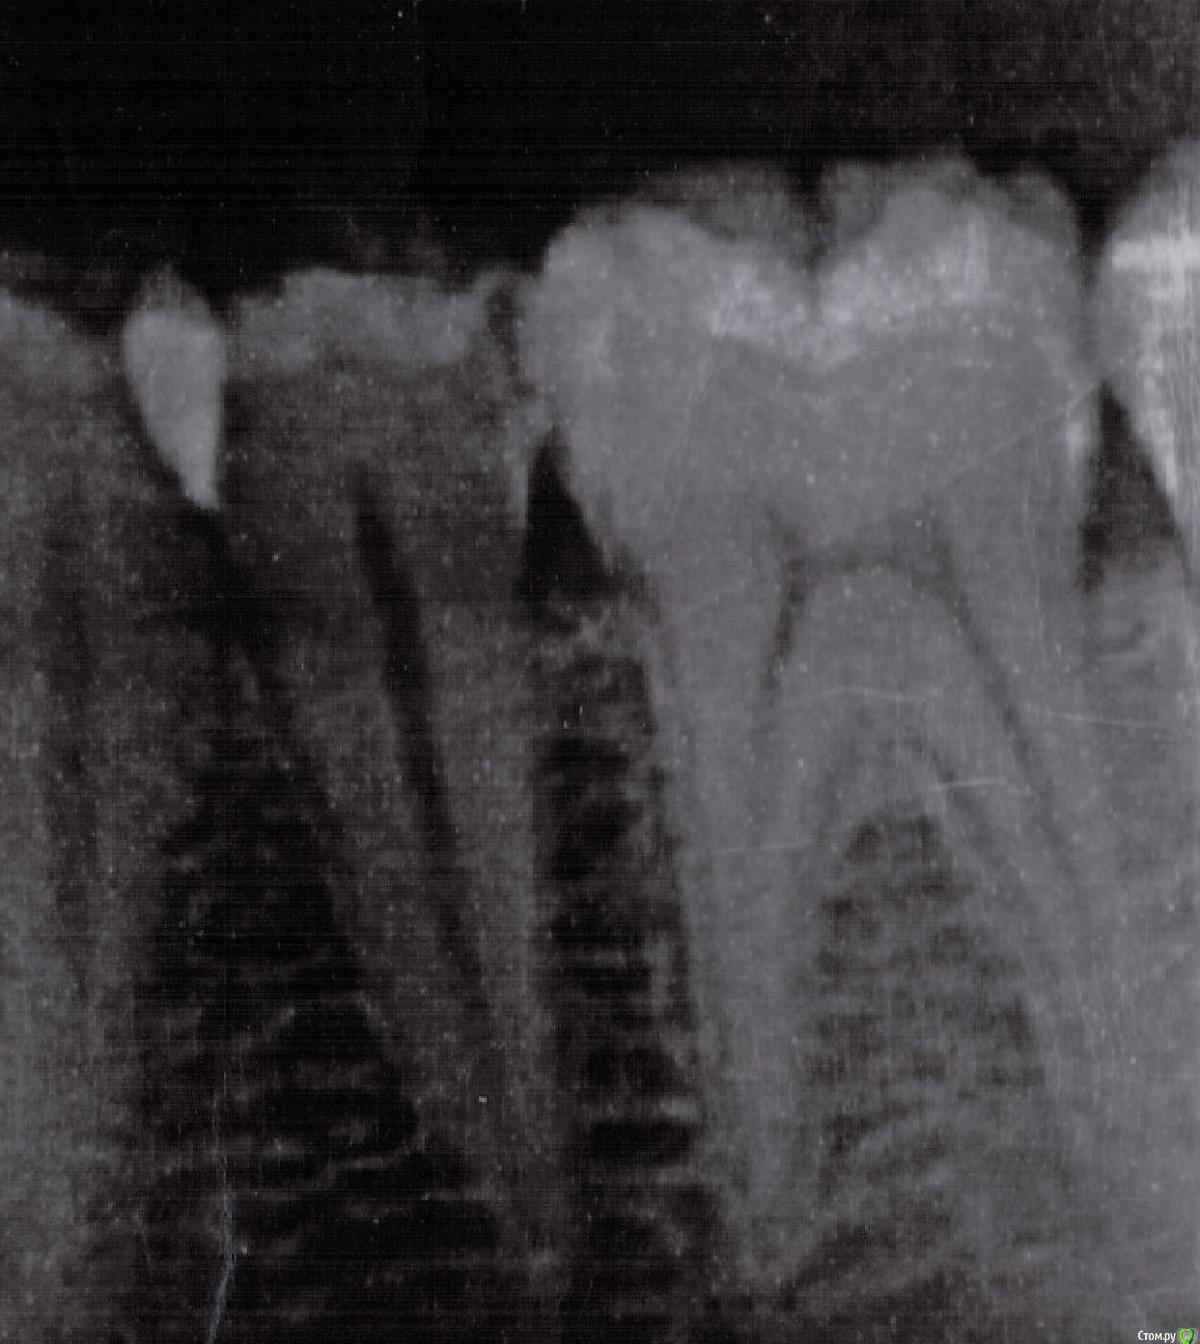

user7887 Опубликовано 24 июня, 2018 Автор Поделиться Опубликовано 24 июня, 2018 (изменено) Покажите свои снимкиВот рентген снимок,фото к сожалению нету,до этого не фоткал,а теперь проблемное место между зубов( Изменено 24 июня, 2018 пользователем user7887 Ссылка на комментарий

red_butler Опубликовано 24 июня, 2018 Поделиться Опубликовано 24 июня, 2018 Качество снимка не позволяет его интерпретировать Ссылка на комментарий

user7887 Опубликовано 24 июня, 2018 Автор Поделиться Опубликовано 24 июня, 2018 Качество снимка не позволяет его интерпретироватьОк,вечером отсканирую) Ссылка на комментарий

user7887 Опубликовано 24 июня, 2018 Автор Поделиться Опубликовано 24 июня, 2018 Снимок в качестве Ссылка на комментарий